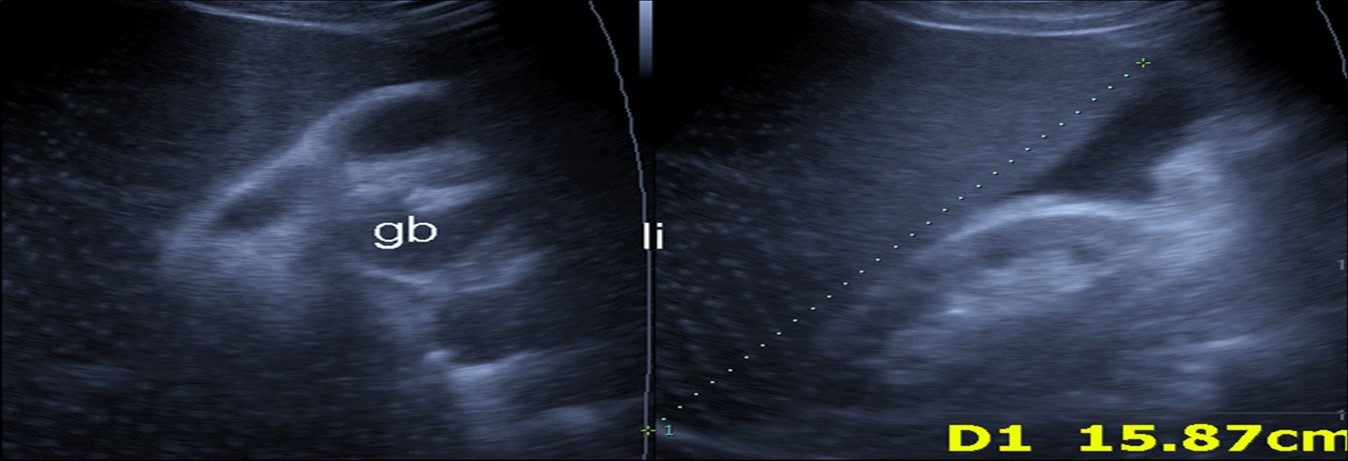

Abdominal ultrasound may revealed any of the followings:-Mild hepatomegaly with echogenic parenchyma and ascites in cases with hepatic impairment (Figure 4, Figure 5) ,thick walls of gall bladder with mildly dilated Common bile duct suggesting of biliary stasis and cholecystitis (Figure 6) .Abnormal renal echogenicity (Figure 7), suprarenal gland enlargements with heterogeneous texture ,splenic wedge shape area of hypoechogenicity ,thickened walls of bowel mainly the rectosigmoid region ,dilated bowel loops with free peritoneal fluid, and gases in the bowel wall with mesenteric and portal vein gases suggesting of bowel wall infarction13.

Figure 4.Real time ultrasound showing thickened wall of gall bladder (gb) with dilated Common bile duct (cbd) in patient with severe Covid-19.

Figure 5.Real time ultrasound showing mild hepatomegaly (li), ascites and thickened gall bladder wall(gb).